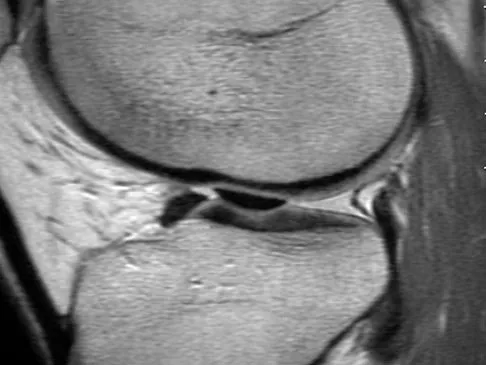

A 35-year-old woman who is a recreational runner reports posterior knee pain and tightness in the knee with flexion during running. She denies any history of trauma. Examination reveals normal patellar glide and tilt and no patellar apprehension. Range of motion is 5 degrees to 120 degrees, and quadriceps function and knee ligamentous examination are normal. Radiographs are normal. An MRI scan is shown in Figure 18. What is the most likely diagnosis?

Explanation